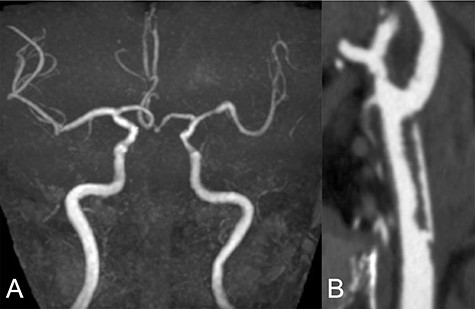

A 69-year-old male visited the emergency department presenting right hemiplegia and total aphasia. The final safety confirmation was 9-h ago. The National Institutes of Health Stroke Scale score was 10. Diffusion weighted imaging (DWI) in magnetic resonance imaging showed high signal intensity in the left frontal lobe and basal ganglia. Magnetic resonance angiography (MRA) revealed a left CCA occlusion with collateral flow via anterior communicating and posterior communicating arteries (Fig. 1A). Computed tomography angiography (CTA) scanning also showed left CCA occlusion without aortic dissection (Fig. 1B). We could not find any clinically significant problem of the patients except atrial fibrillation detected on an electrical cardiogram. We initiated anticoagulant treatment based on finding chronic atrial fibrillation.

MRA demonstrated left CCA occlusion with collateral flow via anterior and posterior communicating arteries (A). CTA showed left CCA occlusion without aortic dissection (white arrow: B).